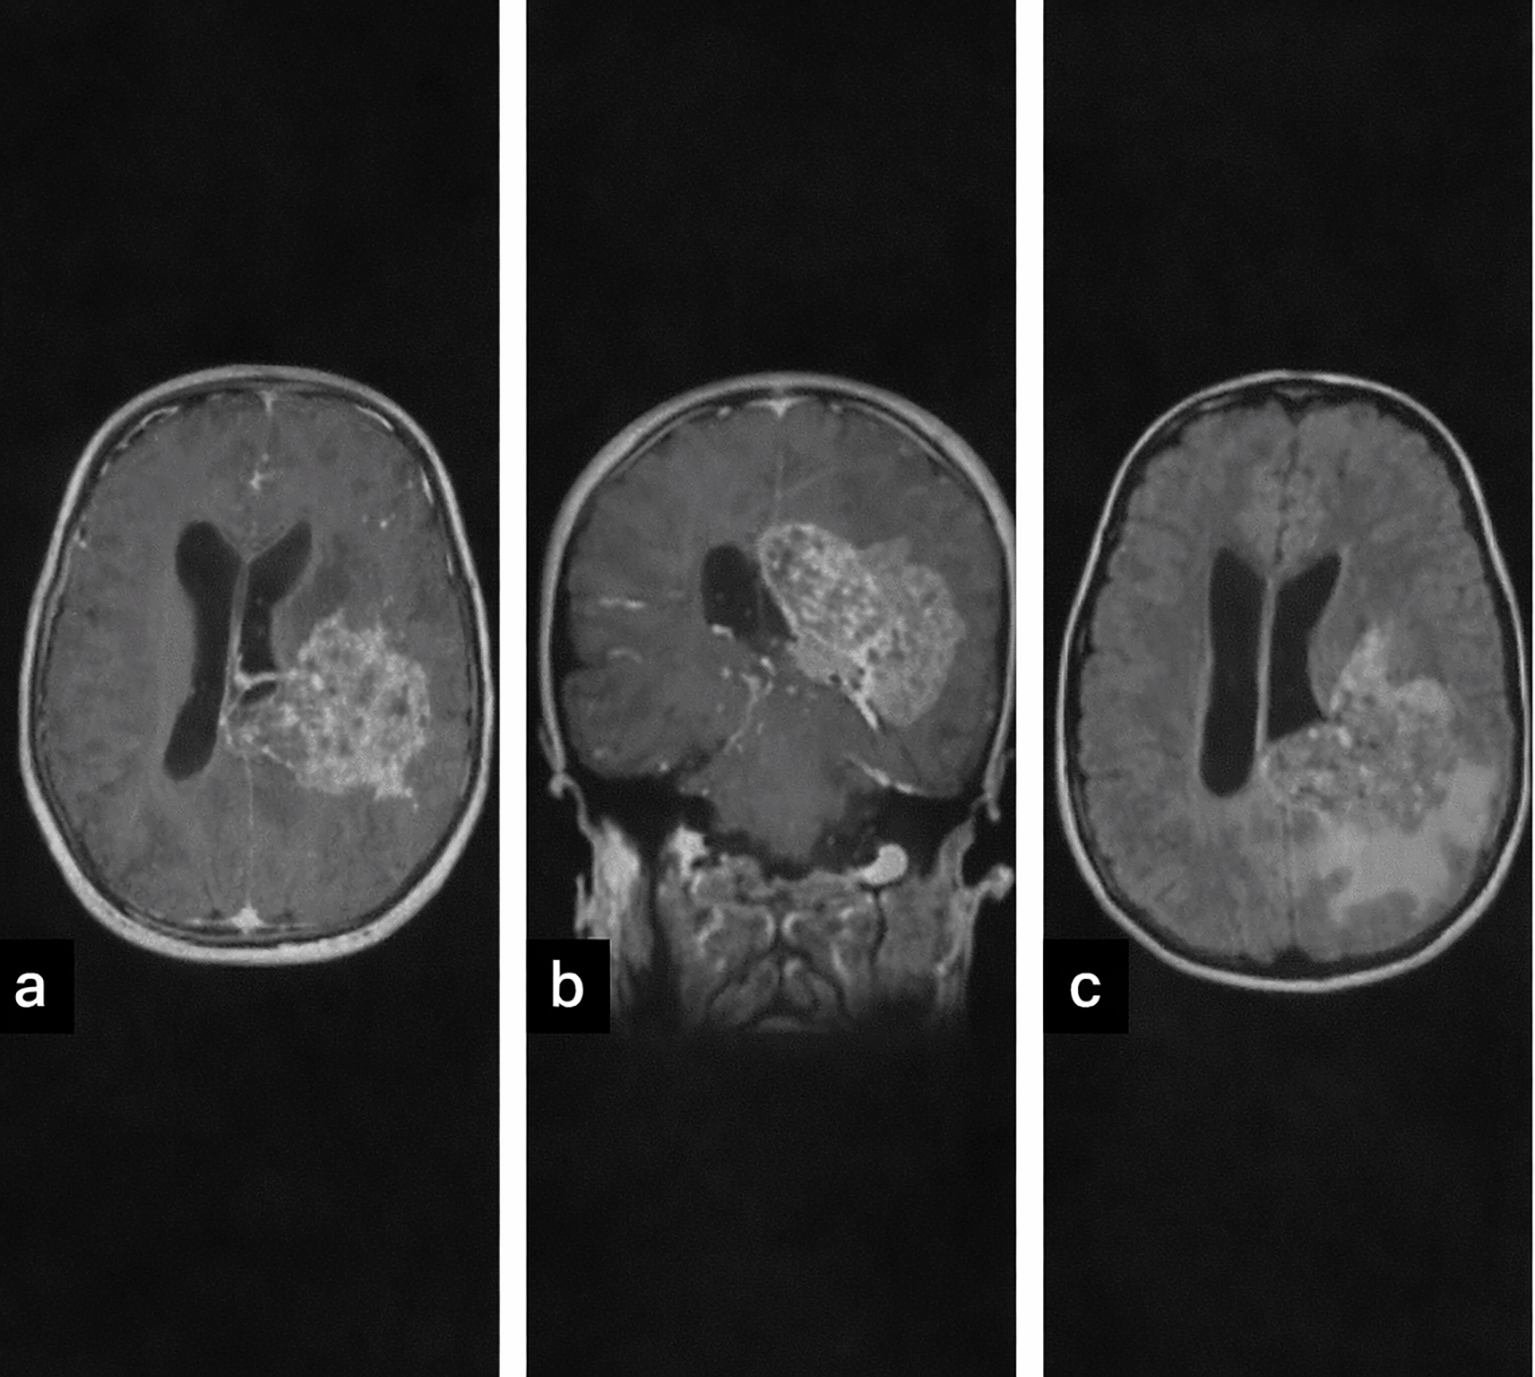

| 5 (CPC) | 9 F | Generalized tonic-clonic seizure; right hemiparesis, papilledema | Heterogeneous, hyperdense, calcifications, hemorrhage, perilesional edema; heterogeneous enhancement, parenchymal invasion (Figure 3) |

Tumors were located in the lateral ventricles in five cases (Figure 1), the third ventricle in one case, and the fourth ventricle with extension to the cerebellopontine angle (CPA) in one case (Figure 2). CT imaging (performed in six patients) showed lobulated intraventricular masses that were iso- to hyperdense with homogeneous enhancement in CPPs, frequently associated with hydrocephalus. CPCs appeared heterogeneously hyperdense with intense enhancement and intratumoral calcifications in two of three cases.

MRI (performed in five patients) demonstrated variable signal characteristics. CPPs were typically well-circumscribed and intensely enhancing, while CPCs appeared heterogeneous (Figure 3), with areas of calcification, hemorrhage, and parenchymal invasion. Hydrocephalus was present in the majority of cases ( Table 1).